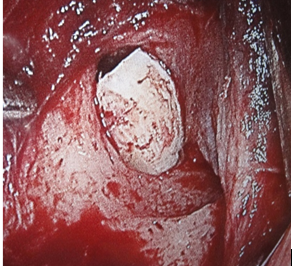

After got the costal cartilage through an incision at the lever of 7 arch costal, the graft is shaped like a projectile. Figure 2A and Figure 2B.

Figure 2A The cartilage costal graft before shaped for introduction in the pocket by an oral approach.

After shaped, the graft is inserted behind the pyriform aperture. Figure 3, 4, 5.

Figure 3 Close of operative view of implants placed along the lateral nasal wall just behind the piriform aperture and under the periosteum of the nasal mucosa.